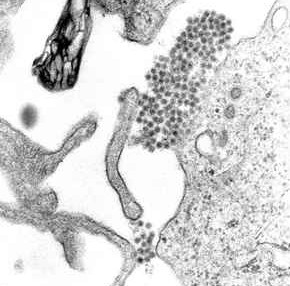

পোলিওভাইরাস ছবিটায় সৃতিকাতর করে দিলেন।

১৯৮৫ সালে পরিবার পরিকল্পনা মন্ত্রনালয়ের অধীনে পরিচালিত টিকাদান কর্মসূচিতে সরকারী ক্যাম্পেইনের পোস্টারে দেখতাম/।